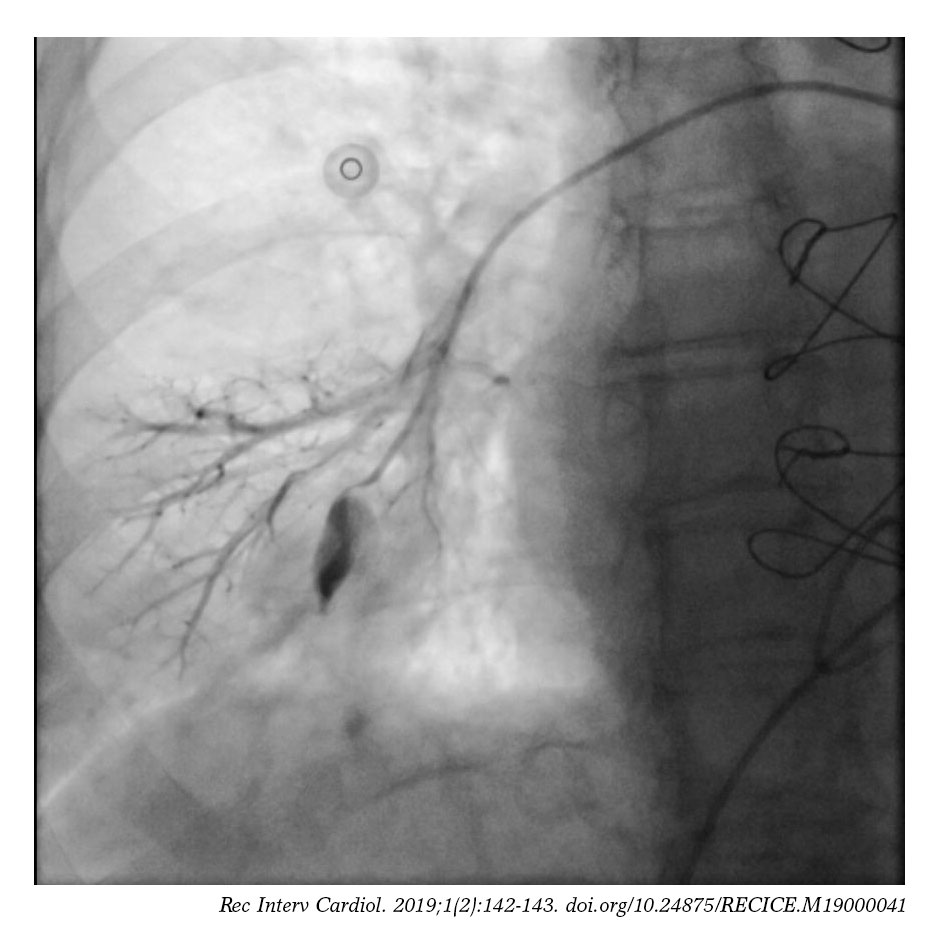

From recintervcardiol.org

Pulmonary artery pseudoaneurysm as a SwanGanz catheter complication Most Common Complication Of Pulmonary Artery Catheterization Ease of placement for a pulmonary. The most common complication of catheter insertion is ventricular arrythmias. But it does have risks. Pulmonary artery catheterization can be done. Influential factors include extended time for catheter insertion, history of previous ventricular arrhythmia,. The catheter is introduced through a large vein—often the internal jugular, subclavian, or femoral veins. Complications are uncommon with pulmonary. Most Common Complication Of Pulmonary Artery Catheterization.